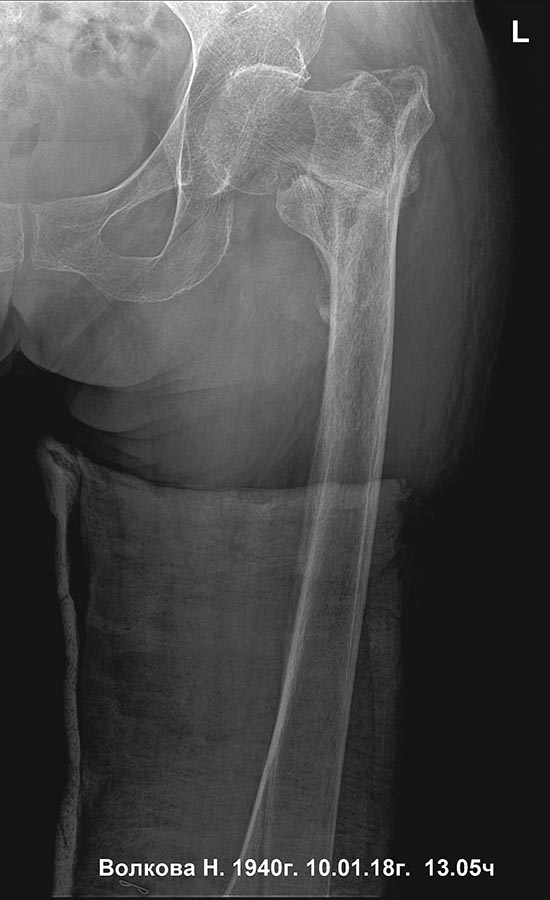

[Ortho] Сросшийся чрезвертельный и перелом н\3 бедра

прямая проекция